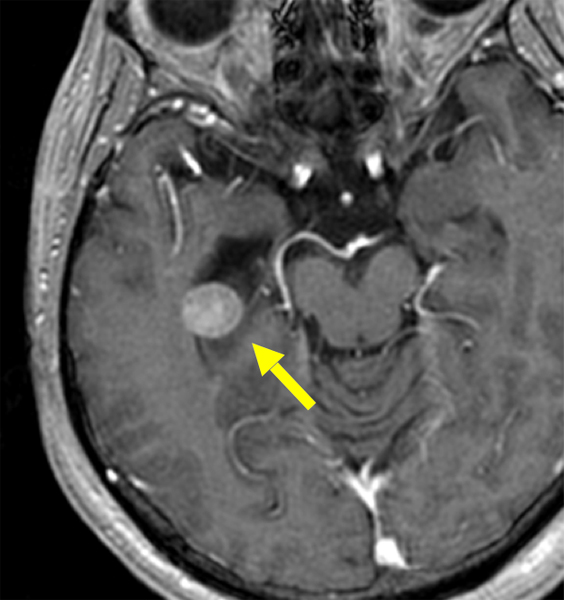

中枢神経原発悪性リンパ腫 治療経過の一例

①初診時

②手術後

③MTX3コース

+

放射線治療後

④1年後

- 小脳の悪性リンパ腫

- 手術+大量メトトレキサート療法3コース+全脳放射線治療を行いました(全ての治療が完了するまでに3ヶ月を要しました)

- 1年以上、腫瘍の再発なく経過しています